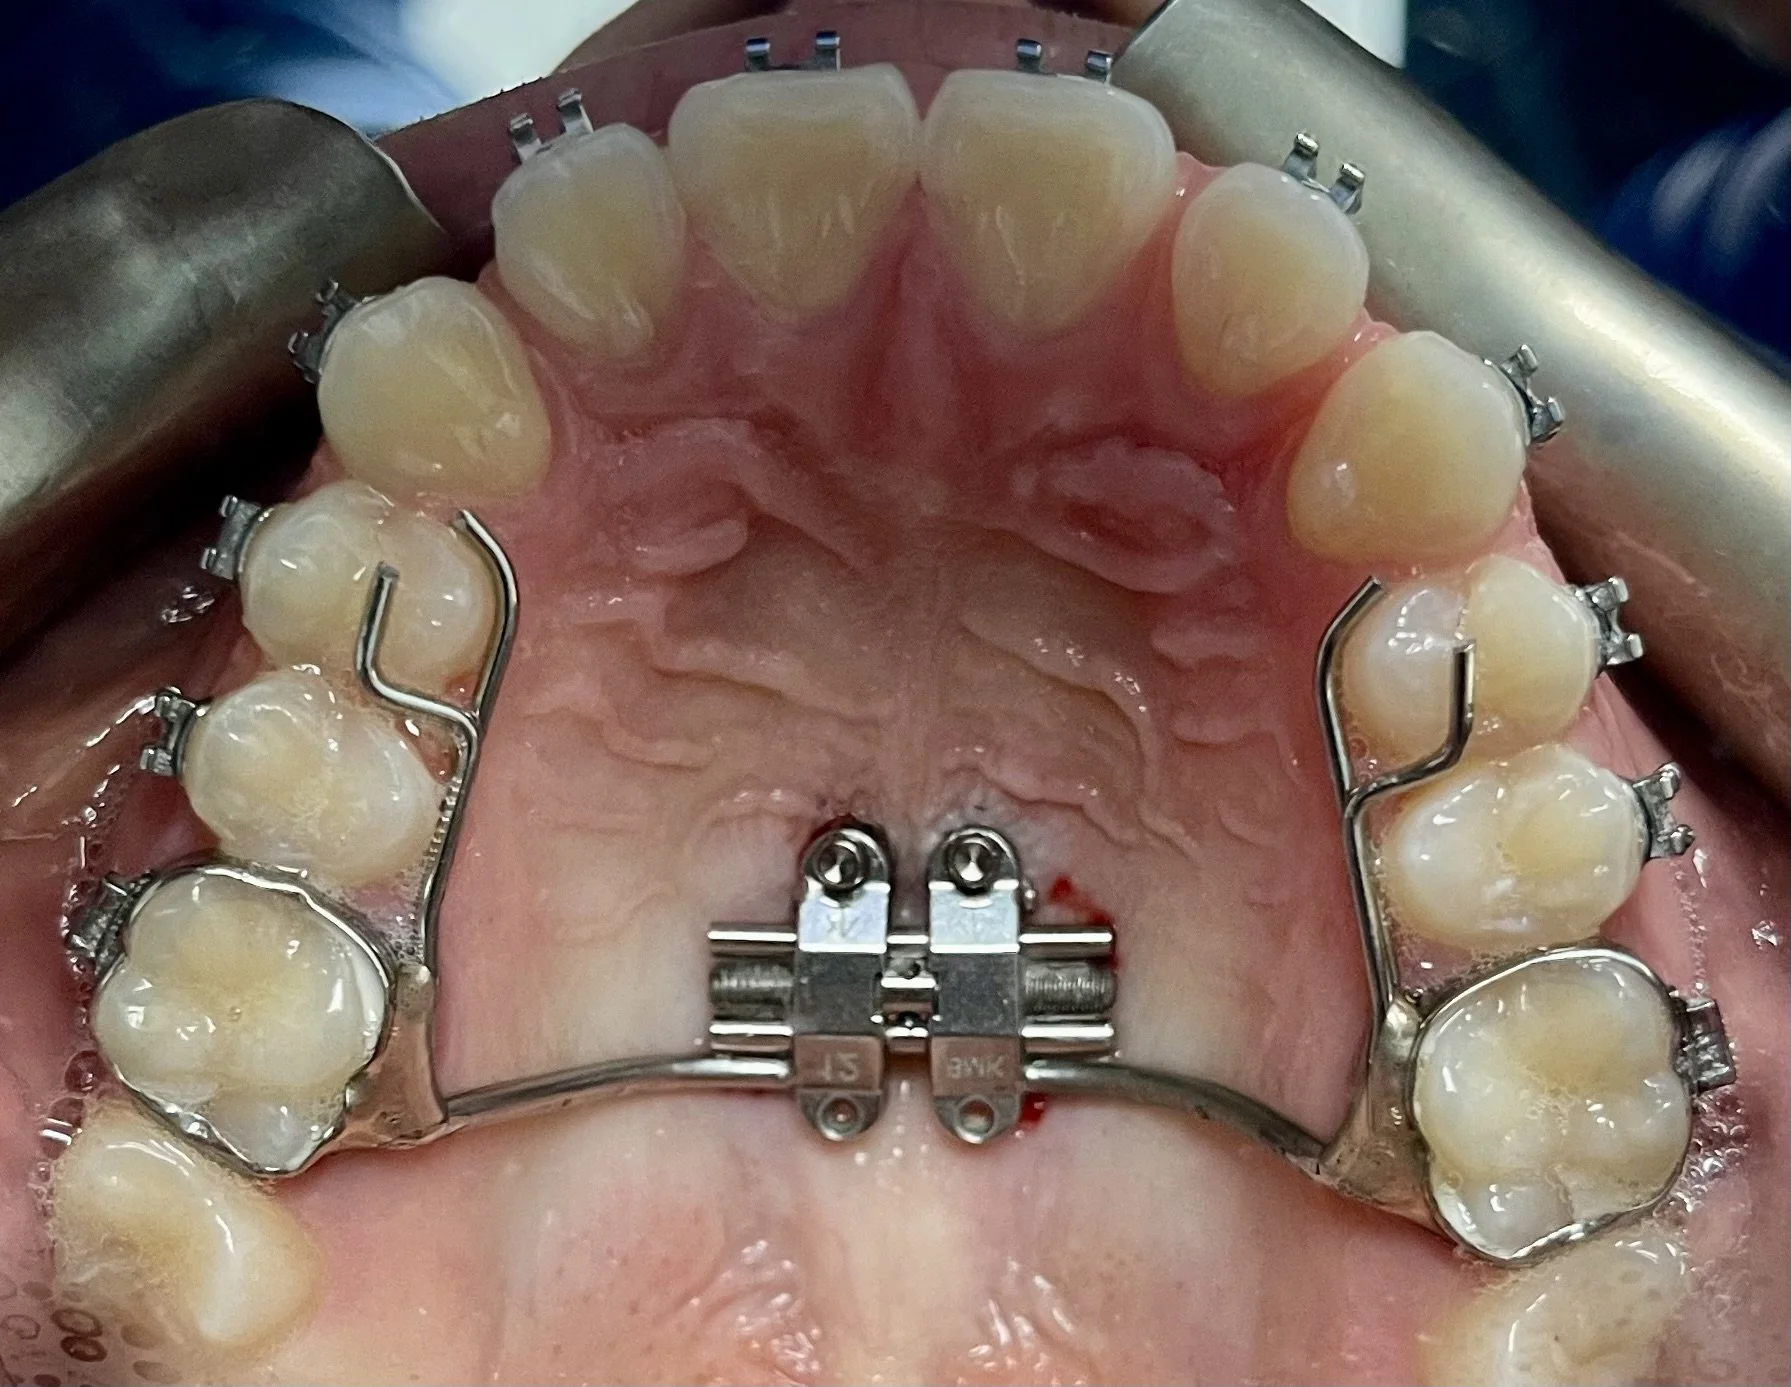

MARPE & Jaw ExpansionMARPE وتوسيع الفك

Miniscrew-Assisted Rapid Palatal Expansion — widening the jaw and nasal airway without surgery, in adults.توسيع الحنك السريع بمساعدة المسامير — توسيع الفك والمجرى الهوائي الأنفي بدون جراحة.